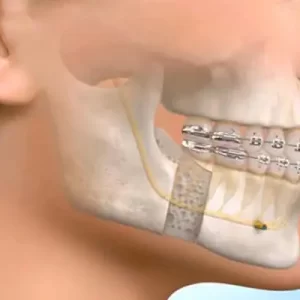

Ağız Diş ve Çene Cerrahisi

Ağız, Diş ve Çene Cerrahisi,ağız içerisinde bulunan bütün yumuşak dokuların ( yanak, dil, tükürük bezleri, dudak vb.) dişin, çenelerin ve çene eklemlerinin her türlü ağrı, sızı ve rahatsızlığını, teşhisi, cerrahi tedavisi gerçekleştirilir. Yapılacak işleme ve hastanın durumuna göre yapılması planlanan cerrahi işlemler, bilinçli sedasyon, genel anestezi ya da lokal anestezi yapılmaktadır. Ağız, Diş ve Çene...